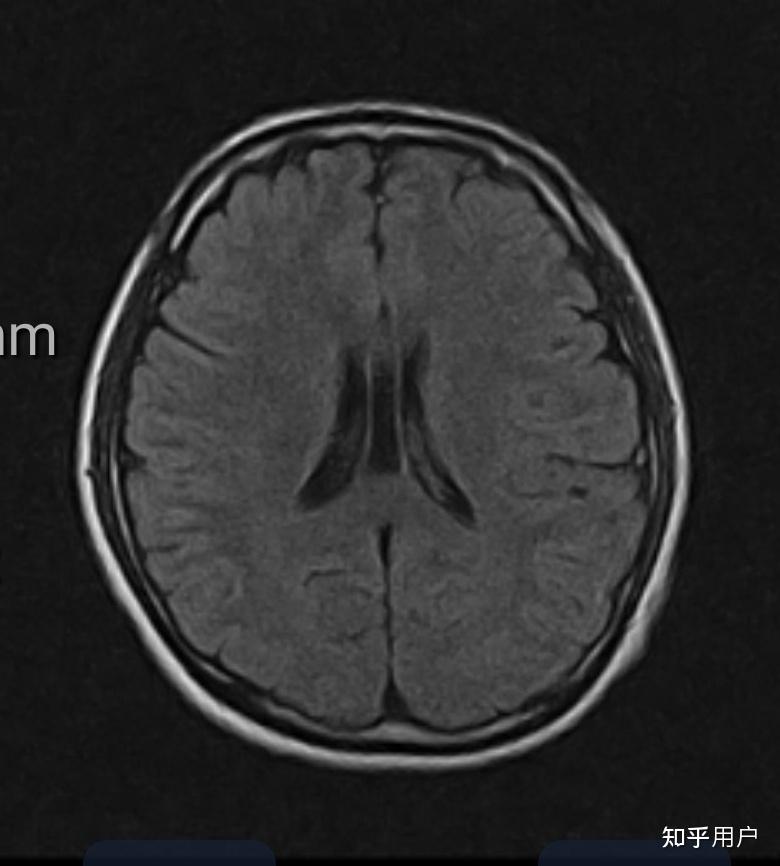

透明隔腔的影像学及临床意义【一文读懂】

透明隔间腔的影像学及临床意义